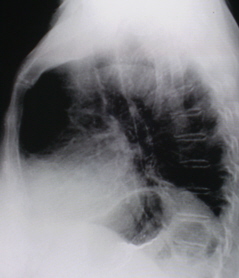

Нами неоднократно обнаруживался данный феномен, при расшифровке цифровых флюорограмм (иллюстрации 2, 3, 4, 5). В последующем, при исследовании органов ЖКТР выявлялась ГПОД.

Иллюстрация 3. Слева базально и латерально определяется некоторое снижение прозрачности легочной ткани. Рядом с сердечной тенью определяется тонкостенное «полостное образование».